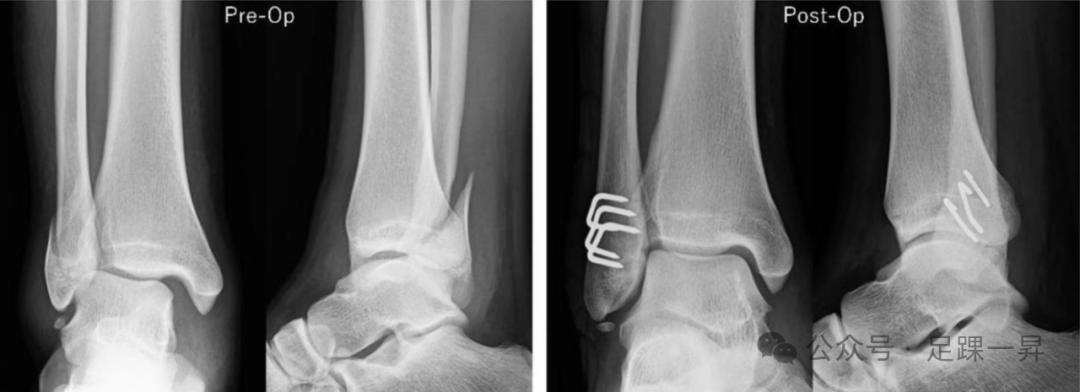

图示Weber B型外踝骨折采用抗滑动钢板固定患者的术前和术后正侧位X线片。

图示多枚镍钛合金骑缝钉固定患者的术前和术后正侧位X线片。